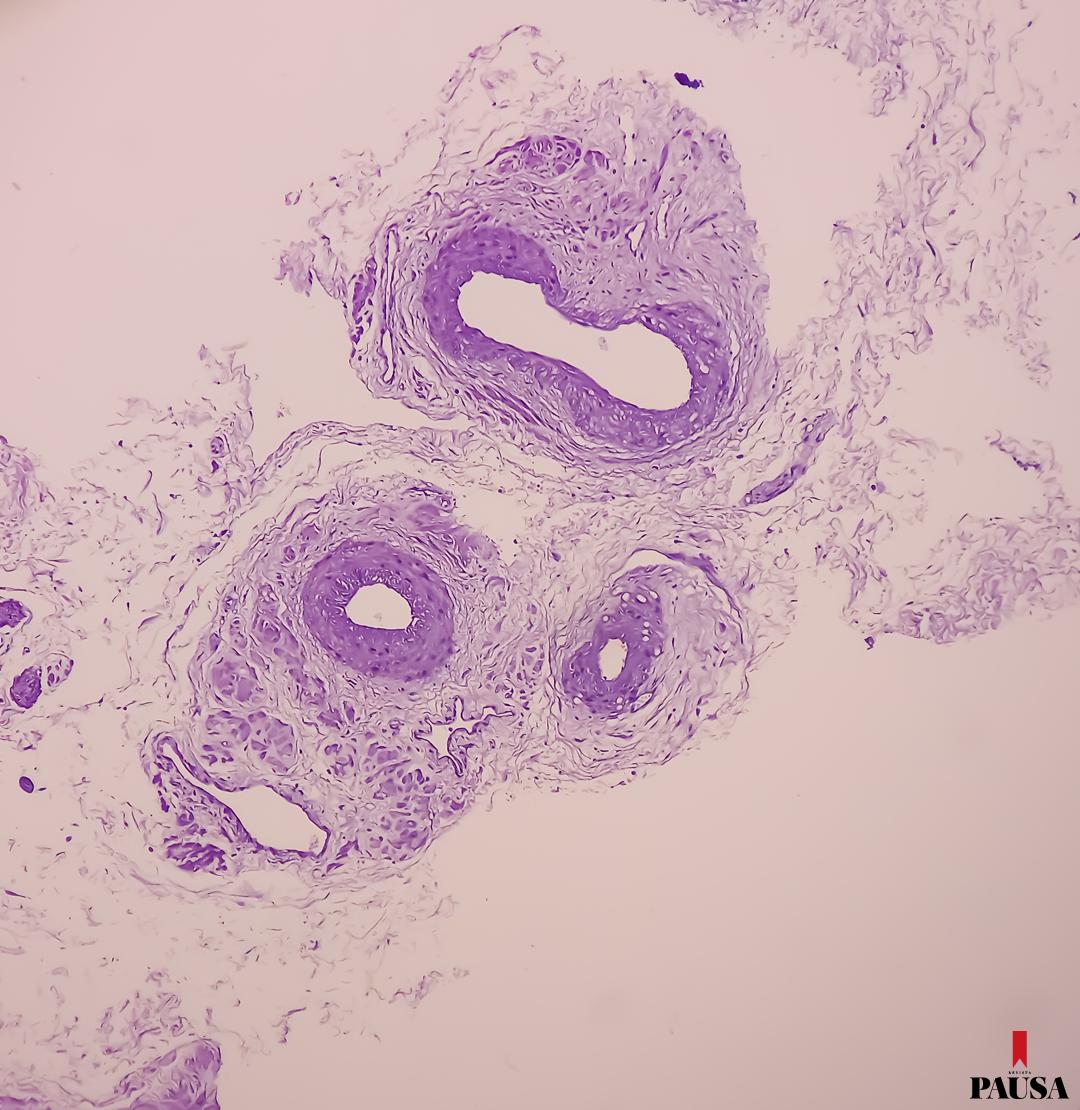

Hoy, el estudio de antígeno prostático específico (PSA) es la principal herramienta de detección temprana, disponible en la mayoría de los laboratorios de los servicios de salud del país. Generalmente es el primero de los procedimientos a tener en cuenta. Este análisis se complementa con imágenes o el tacto rectal, en casos específicos. “En los últimos años, la tecnología ha avanzado considerablemente y permitió realizar pruebas más precisas y menos invasivas”, comenta Vázquez.

Sobre estos temas conversamos con el doctor Arnaldo Vázquez, médico oncólogo, especialista en Anatomía Patológica y jefe del Programa Nacional de Prevención, Detección Precoz y Tratamiento del Cáncer de Próstata, del Ministerio de Salud.